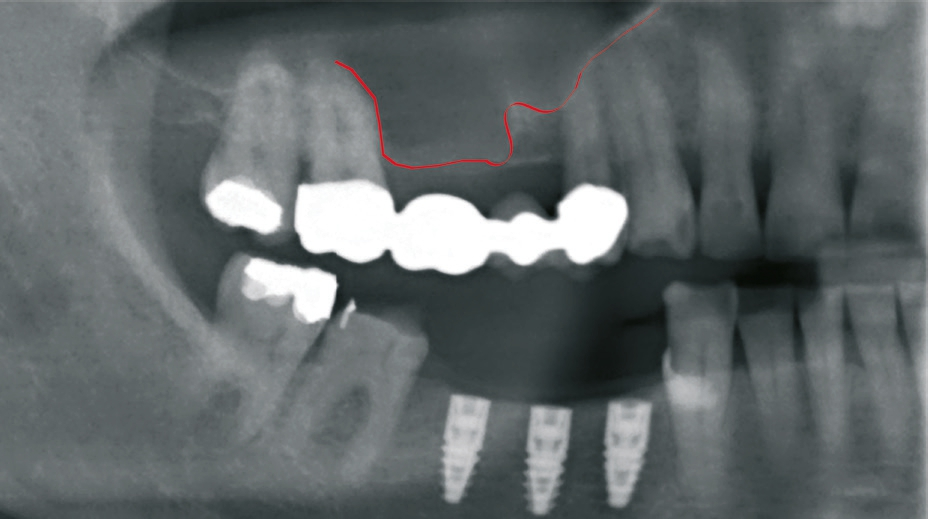

Patient 2: männlich, 71 Jahre alt, Anamnese: koronare Herzkrankheit; Diagnose: zahnloser Kiefer resp. nicht erhaltungswürdiger Zahn 11, insuffizienter Zahnersatz. Knochenersatzmaterial: maxgraft® (botiss) (Abb. 11 und 12).

Dr. van Orten